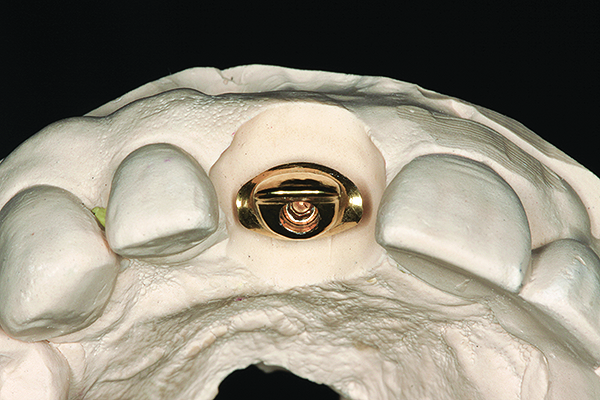

Fig 14. The virtually designed abutment.

Figure 14

The implant impression, along with a cast of the opposing arch and shade, were sent to a commercial dental laboratory for fabrication of a master cast. A signed work order and the master cast were then sent to the BellaTek® Production Center (BIOMET 3i) for a lab-designed abutment (LDA) (Figure 14). A BellaTek® abutment was milled from a solid blank of titanium, and a gold-colored titanium-nitride coating was applied to impart a warm color through the thin marginal peri-implant tissues.